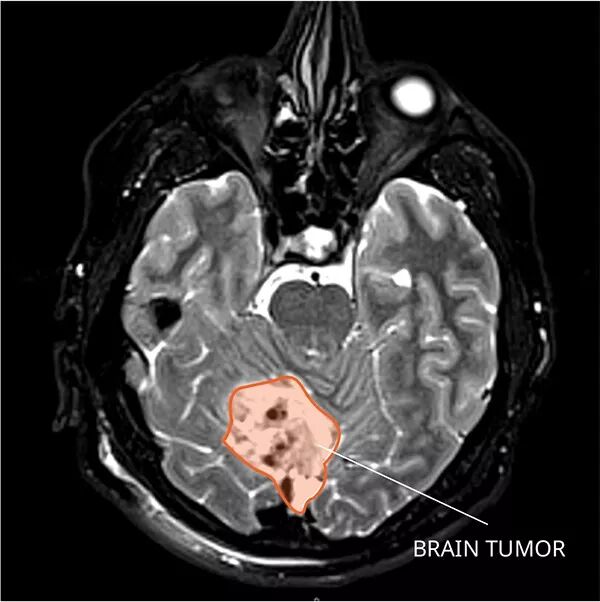

研究性CAR T细胞疗法已经在几种类型的儿童癌症的小鼠模型中显示出前景,包括髓母细胞瘤。图片来源:国家癌症研究所

脑瘤

不仅如此,就连一般药物无法跨越的血脑屏障,令人闻风丧胆的脑癌,B7-H3 CAR-T细胞依旧不在话下,在髓母细胞瘤的小鼠中,B7-H3 CAR-T组小鼠的病灶几乎被完全清除,而对照组小鼠的肿瘤迅速进展扩散。

左边为接受B7-H3 CAR-T治疗小鼠;右边为CD-19 CAR-T治疗小鼠;图中红蓝色为小鼠肿瘤